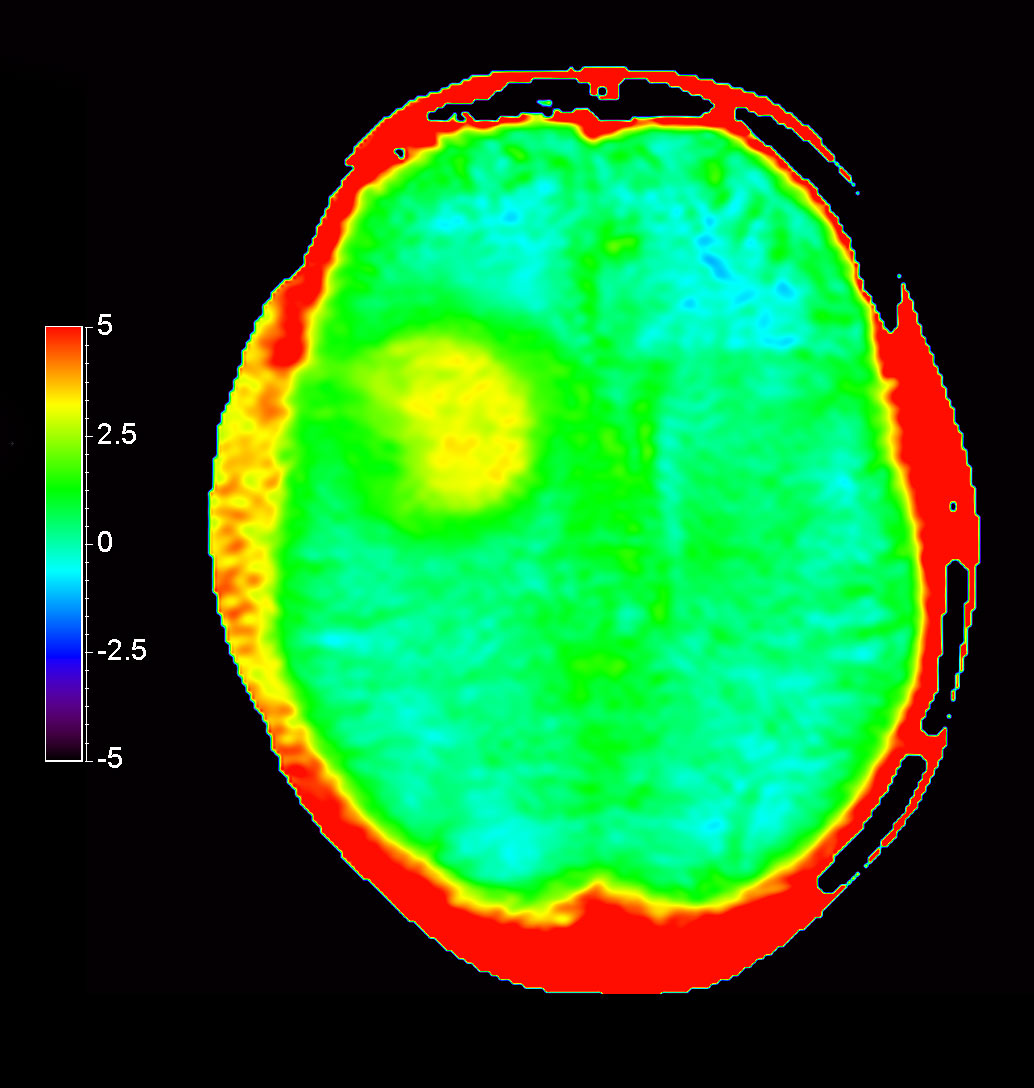

Patient with a revasculerized area with small bleedings. Diagnosed as malignant glioblastoom.

Axial 3D APT